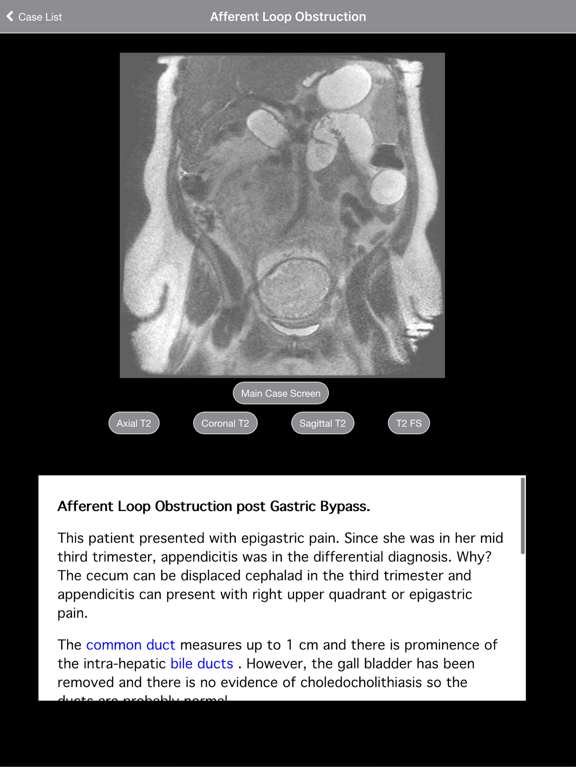

View and analyze MRI scans of patients with interactive case studies. Identify acute abdominal conditions through detailed imaging. Access cases of right lower quadrant pain in pregnancy.

With its 2010 release, "Radiology 2.0: One Night in the ED," became the first radiology teaching file to simulate reading scans at a PACS workstation. The second installment arrived in 2014 and is now updated! Volume 2. Pregnant Appendicitis: This teaching file is designed to introduce you to the appearance of acute abdominal processes on MRI. Cases are taken from my experience performing MRI in pregnant patients. This volume contains 41 cases of common causes of right lower quadrant pain including appendicitis, bowel obstruction, ovarian torsion, renal obstruction, and pyelonephritis.   After viewing these cases you will be comfortable interpreting MRI of the acute abdomen in both pregnant and non pregnant patients. Each case is presented as a complete MRI scan that you can scroll through as if at a PACS workstation. Multiple sequences in multiple planes are presented for every case. Each exam is discussed in an interactive format. Important findings are highlighted with arrows, circles, and colorful schematics. Multiple examples of each type of pathology are presented so you can learn by repetition. Varied appearances of similar diagnoses are included. The first case in each section has a comprehensive description of the featured disorder. Subsequent cases utilize shorter descriptions and focus on the pertinent findings. Entire cases are presented as scrollable stacks. Extensive, interactive discussions accompany each case and include labeled images that highlight pathologies and relevant findings. Rather than use static images to teach specific diagnoses, Radiology 2.0 uses stacks of images to actually teach the reader how to approach and interpret scans. This incredible series is available to the medical community at no charge. The interface incorporates image zoom and pan. In addition, both portrait and landscape orientations are supported. This intuitive teaching file series is perfect for practicing radiologists, radiology residents, medical students in radiology, and other physicians interested in learning how to interpret images. The extensive content is contained within the app for offline viewing. You can now learn radiology on-the-go and in the palm of your hand, even with a few minutes of spare time throughout the day. Once again, it is completely free and provided as a resource for medical education. No in app purchases. No subscription fees. Additional: - Dr. Daniel Cornfeld is a consultant radiologist at Hauora Tairawhiti in Gisborne, New Zealand. Prior to that he was an Associate Professor of Diagnostic Radiology at Yale University School of Medicine. The narratives contain his opinions (based on the medical literature) and reflect the way he would teach if you were one of his students. The information in this app does NOT constitute medical advice and is meant to compliment and augment, not replace, pre- or co-existing medical education. Neither Hauora Tairawhiti nor Yale University School of Medicine have officially endorsed this content.